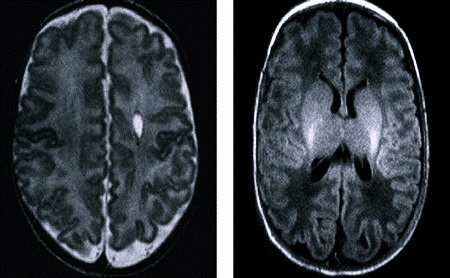

Детям до года легко провести диагностику, так как у них еще не успевает закрыться родничок. При этом достаточно провести ультразвуковое исследование – нейросонографию. Киста анэхогенная и ее легко можно увидеть на экране. Для детей старше года проводят томографию.

Особенно важно провести нейросонографию, ели ребенок рождается недоношенным. Также такая диагностика показана, если новорожденный перенес реанимационные мероприятия при рождении, или ему проводится интенсивная терапия.

Еще один повод – проблемная беременность или гипоксия плода. В таких случаях проводят УЗИ еще в роддоме.

При субэпендиамальной кисте нужно несколько раз в году проводить исследование при помощи МРТ (делается под общим наркозом в закрытом контуре) или МР. Лечение не требуется, если киста не растет. Скорее всего, ткани мозга восстановятся самостоятельно. Такие кисты проходят чаще всего без постороннего вмешательства, но они могут вызывать серьезные осложнения, если кистозная полость увеличивается. Это приводит к тому, что внутри нее накапливается много жидкости, растет давление. Со временем полость начинает давить на прилегающие ткани мозга.